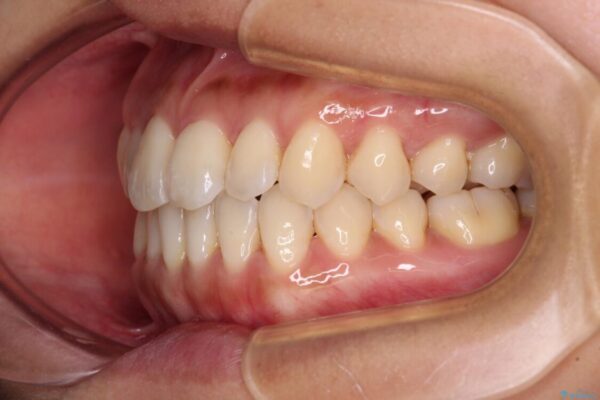

治療後について

装着時間を守ってくださったので、予定通りの期間で終えることができました。インビザライン特有の、奥歯の咬み合わせの問題もなく、しっかりと歯列を改善することができました。

治療後

• 【モニター】前歯のデコボコをインビザラインで改善 治療後画像